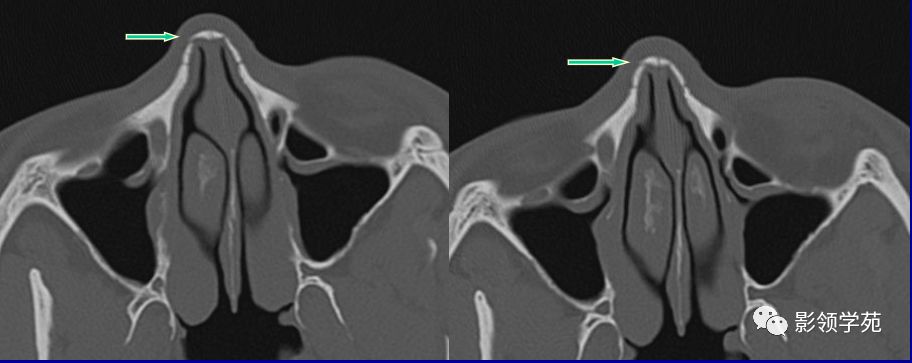

鼻骨横断面HRCT

线性骨折 粉碎骨折

右侧鼻骨线形骨折

鼻骨线形骨折

左侧鼻骨线形骨折